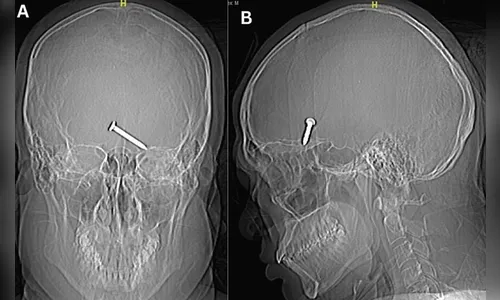

Um raio-x do crânio mostrou que o prego de três centímetros havia se alojado no cérebro do malasiano. Parte do crânio dele foi dilacerada pelo impacto. Apesar da gravidade do ferimento, o homem apresentava bons sinais vitais.